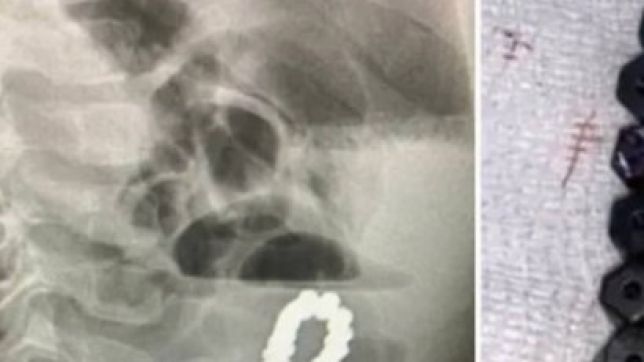

A revelação: as dores na verdade estavam sendo provocadas pela ingestão de um bracelete com contas magnéticas.

Para piorar as coisas, o objeto infiltrado no corpo estava obstruindo os intestinos do menino e até mesmo abrindo buracos no órgão. Para evitar mais danos, os médicos realizaram uma laparotomia de emergência – uma operação na qual os cirurgiões fazem uma incisão na cavidade abdominal – e removeram a pulseira, que consistia em 18 contas magnéticas hexagonais. Eles também fecharam os buracos na parede intestinal do pequeno paciente.

Foto: Reprodução